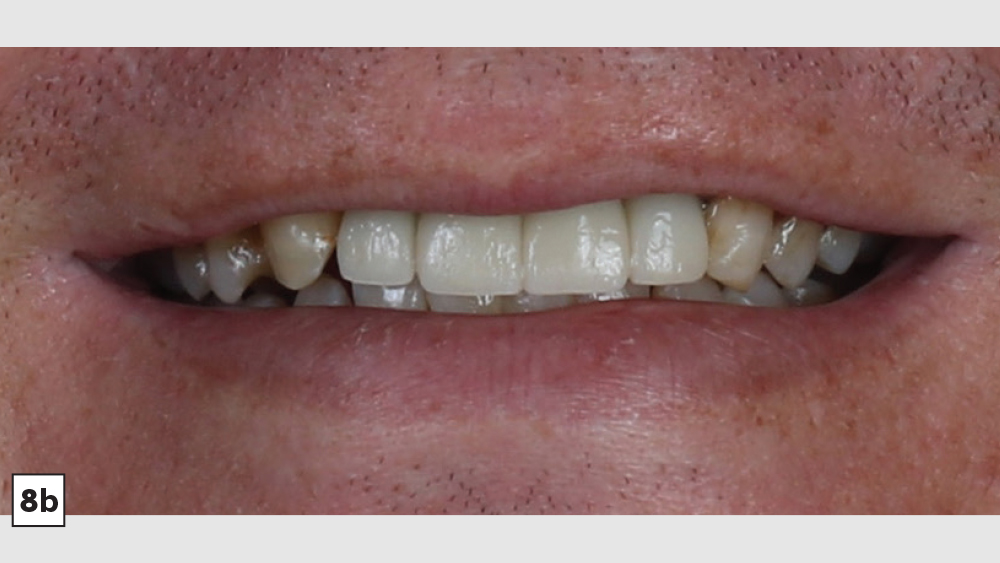

This patient came to me with four missing anterior teeth in positions #7–10. He had been missing these teeth for some time and was wearing a temporary denture to address the cosmetic issue this created. When he came to my practice, he was in a financial position to solve the problem permanently with implant restorations. Based upon the anterior space available and the fact that the patient’s surrounding tissue was in good health, I chose to move forward with Hahn™ Tapered Implants and BruxZir® Esthetic restorations.

There’s nothing more rewarding than when patients return to your office for additional dentistry because they were so thrilled with the results of the previous procedure you performed for them. This particular patient followed through with the additional treatment I had previously recommended.